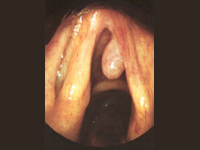

- Cirurgia de Sinus. Només si la medicació falla o l'obstrucció nasal no es pot corregir amb medicaments, es pot considerar la cirurgia. La cirurgia endoscòpica es recomana per a certs tipus de desordres sinusals. L'endoscopi permet al cirurgià veure directament l'interior del nas, i al mateix temps, eliminar teixits i pòlips i netejar els canals estrets que hi ha entre els sinus. La decisió d'usar anestèsia local o general es farà sempre d'acord amb el pacient, depenent de les seves circumstàncies personals.